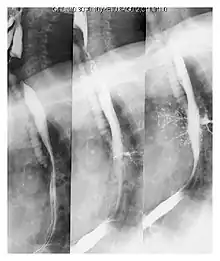

![]() | |

| Upper gastrointestinal series at the level of the esophagus, showing pulmonary aspiration of the radiocontrast agent | |